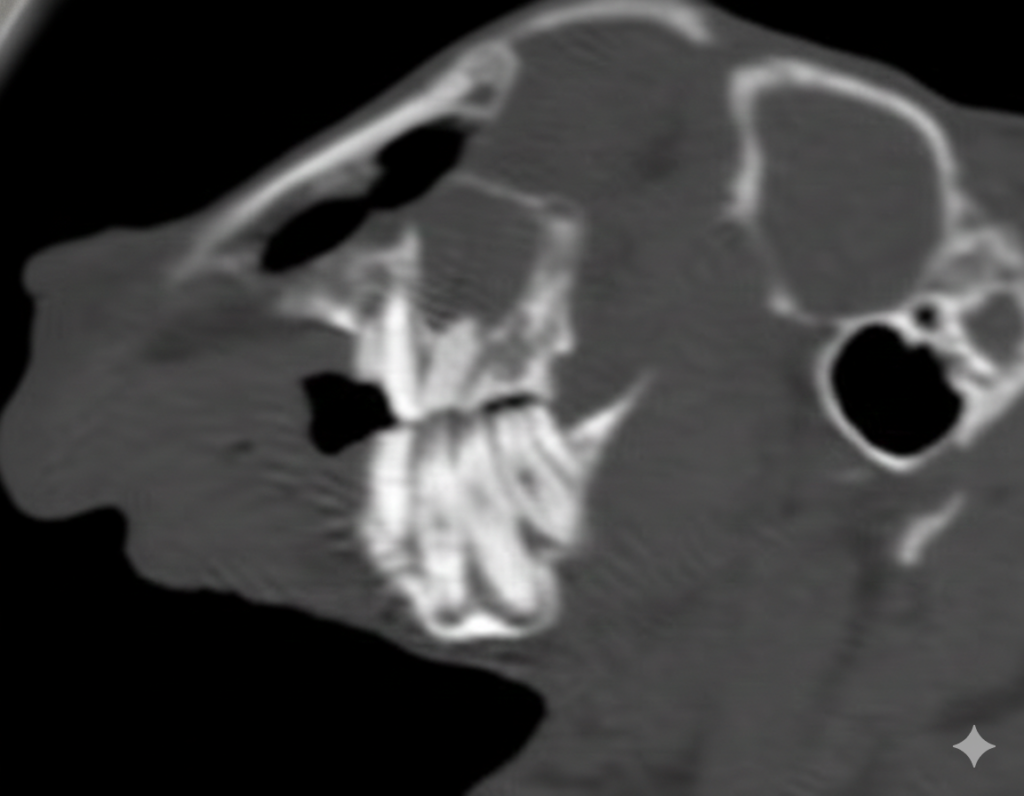

正確に診断するにはCT検査が必要になります。ウサギは無麻酔で撮影が可能です。

歯根はX線検査をで評価をしますが、左右、上下が重なっての評価になり、全ての異常を確認することはできません。

基本的には切歯を肉眼で観察し、口の中に耳鏡などを入れて臼歯を観察します。ただし目視で観察できるのは歯肉から出ている歯冠のみで歯根は見れません。